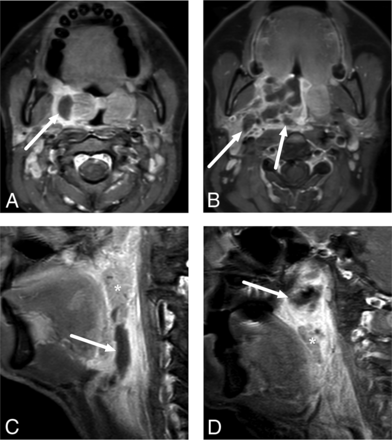

All patients had a final clinical diagnosis of tonsillar or pharyngeal infection. Of those with an abscess, 98 (89%) underwent an operation and an abscess was surgically confirmed in 96 patients, suggesting a PPV of 0.98. We had 2 patients with false-positive findings in whom no purulence was found. Six patients underwent an operation without MR imaging evidence of abscess; among these, 4 had true-negative findings and 2 had false-negative findings. Assuming 15 more patients with true-negative findings (ie, patients with a tonsillar infection but no abscess who recovered uneventfully following conservative treatment), we found a sensitivity, specificity, and accuracy of 0.98, 0.90, and 0.97, respectively, for an MR imaging diagnosis of an abscess (Table 2). In our experience, craniocaudal or lateral extension of an abscess far from the tonsil is the most reliable imaging sign of parapharyngeal or retropharyngeal extension (Fig 2). This morphologic assessment of deep extension had an overall sensitivity, specificity, and accuracy of 0.88, 0.90, and 0.89, respectively, as well as substantial agreement in the interobserver analysis (92% agreement, κ = 0.75).

Examples of uncomplicated PTA (A) and abscesses with deep extension (B–D) in different patients. In uncomplicated PTA, the abscess is retained within the pharyngeal constrictor muscle (A). In axial images, a deeply extending PTA is often lobulated and reaches laterally toward the parapharyngeal space, beyond the pharyngeal constrictor muscle (B). In sagittal images, a deeply extending PTA can reach far inferiorly (C) or superiorly (D) from the palatine tonsil (asterisk). The arrows denote abscesses.

The primary objective of emergency imaging is to provide a correct diagnosis and an anatomic basis for managing deep neck infections. Although PTAs do not typically require imaging, the patients in the current study underwent emergency MR imaging because either prior procedures had not yielded pus or a deep extension of the disease was primarily suspected. In our study of 98 patients with a radiologically diagnosed abscess who were later treated surgically, 96 had an abscess verified by the criterion standard. Of the false-positives, 1 patient had a hematoma after many puncture attempts. The second case was a very small abscess identified on MR imaging, and no purulence was identified during the operation. We found a sensitivity, specificity, and accuracy of 0.98, 0.90, and 0.97, respectively, for an MR imaging diagnosis of a pharyngotonsillar abscess. These results compare well with those of previous CT studies with the sensitivity, specificity, and accuracy of <0.90.4,10,11 Among the patients needing imaging for tonsillar infection, 37% had a deep extension to the parapharyngeal or retropharyngeal spaces. For the detection of parapharyngeal or retropharyngeal extension, the sensitivity, specificity, and accuracy were 0.88, 0.90, and 0.89, respectively, and interobserver agreement was substantial. In our experience, parapharyngeal or retropharyngeal extension should be suspected if the abscess reaches outside the palatine tonsil borders either laterally, superiorly, or inferiorly (Fig 2). Surgical literature shows that most cases of parapharyngeal abscesses are associated with concomitant PTA, suggesting that they are often direct extensions of PTA.12 Our current results indicate that deep extension can be detected or ruled out accurately by MR imaging.